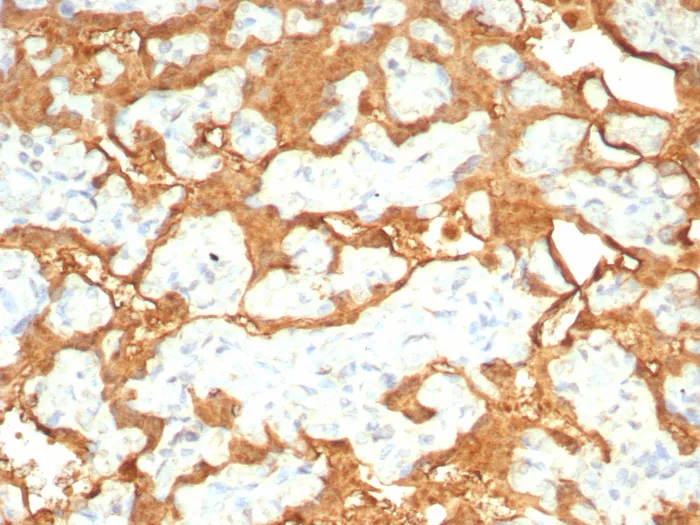

S100P is a 95-amino-acid protein and a member of the S100 family. S100P has been shown to mediate tumor growth, metastasis and invasion through the binding of Ca2+ ions, receptor for advanced glycation end products, cytoskeletal protein ezrin, calcyclin-binding protein/Siah-1-interacting protein and cathepsin D.S100P highly expressed in human placenta, gastrointestinal tract, and esophageal mucosa, but always negative in pancreas and liver. Overexpression of S100P has been detected in several cancers such as breast, colon, prostate, pancreatic and lung carcinomas, and the protein has been functionally implicated in carcinogenic processes. S100P could potentially serve as diagnostic marker, prognostic/predictive indicator and therapy target for different carcinomas.